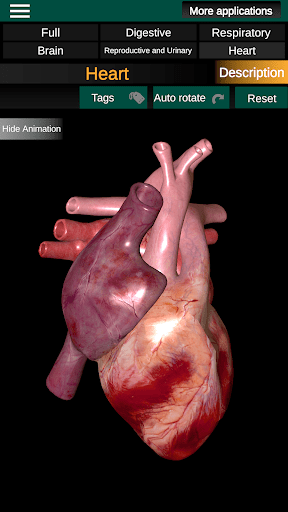

Internal Organs in 3D Anatomy لـ Vodafone Smart N9 Lite

(الأجهزة الداخلية في)

Internal Organs 3D Anatomy 3.4

يمكنك هنا تنزيل ملف حزمة تطبيق أندرويد "Internal Organs 3D Anatomy" الخاصة بجهازVodafone Smart N9 Lite مجانًا، نسخة ملف حزمة تطبيق أندرويد - 3.4 للتحميل على Vodafone Smart N9 Lite اضغط ببساطة على هذا الزر. إنه سهل وآمن. نحن نقدم فقط ملفات حزمة تطبيق أندرويد الأصلية. إذا انتهكت أية مواد موجودة في الموقع حقوقك قم بإبلاغنا من خلال